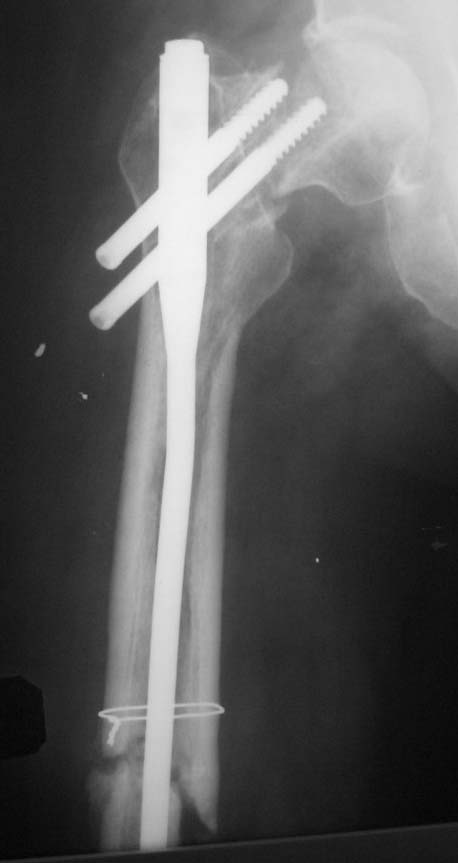

[Ortho] Ложный сустав шейки бедра+перелом в/3 диафиза бедра

Пациент (мужчина), 34 года. Травма в результате ДТП в апреле 2011 года. Проводилось

оперативное лечение закрытая репозиция, остеосинтез AFN. В октябре 2011 года

декортикация, тунелизация, фиксация отломков верхней трети диафиза бедренной кости

проволочным серкляжом, удаление дистального блокирующего винта. На контрольных

рентгенограммах определяется миграция шеечных винтов конструкции. Пациент

передвигается на костылях с дозированной нагрузкой на ногу (полная нагрузка болезненна в

области тазобедренного сустава). Вариант лечения - тотальное эндопротезирование

тазобедренного сустава+остеосинтез верхней трети диафиза бедренной кости (ретроградным

стержнем ЦИТО, пластиной, АНФ). Жду Ваших комментариев